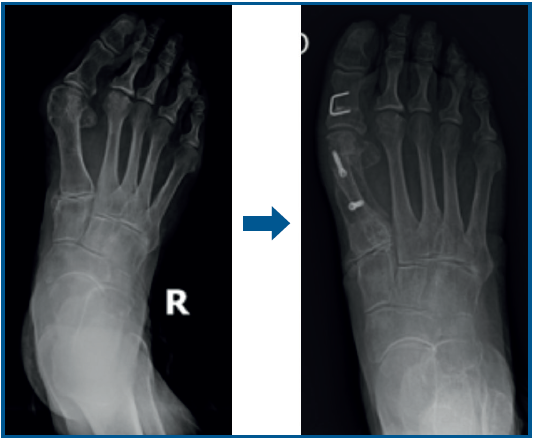

En los 11 casos de hipocorrección de la deformidad, el AHV posterior a la cirugía fue de 18,86° de media (DE: 2,16), partiendo de un AHV considerado severo (> 40) en 8 de los casos y moderado (20-40) en 3 de ellos (Figura 1). En el caso de las hipercorrecciones observadas, la media de AHV tras la cirugía fue de −2,6° (DE: −3,25) (Figura 2). Tanto los casos descritos de hipocorrección como los de hipercorrección no tuvieron repercusión clínica en los pacientes en los que se presentaron, por lo que no fueron necesarios mayores actos terapéuticos posteriores.